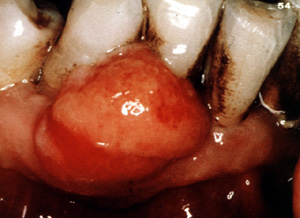

Este ejemplo es bastante vascular. Ha cambiado de sitio al incisivo central hacia lingual. Los granulomas de  celulas gigantes tienen un mayor potencial de crecimiento  que el granulomas periférico y puede cambiar de lugar  los dientes.